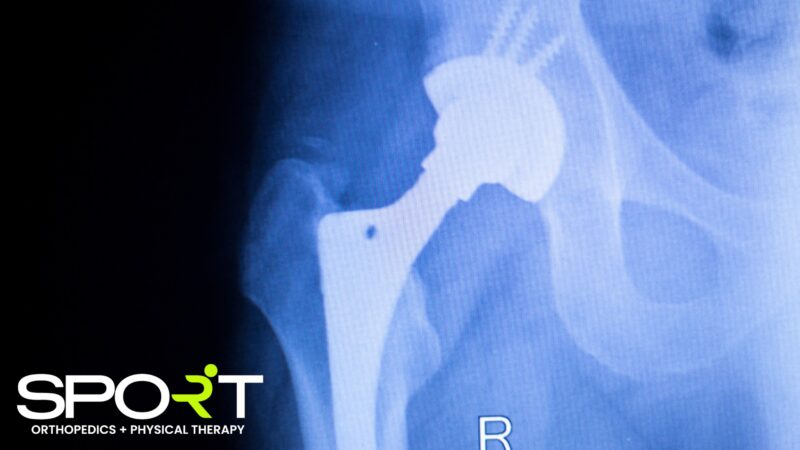

Before the surgeon begins, the surgical site will be cleaned, and hair will be removed. Once this has happened, the orthopedic surgeon will make the incision at the front of the hip joint and separate the muscles so that they can see the injured hip bone. The surgeon will then remove the upper part of the femur and damaged cartilage and bone from the pelvis. After the surgeon removes the bones and cartilage, the hip bone socket, head, neck, and part of the shaft of the femur will be replaced with the artificial joint. When the surgeon has the artificial joint in place, they will take an X-Ray to ensure it has been properly set. Either the surgeon or surgical assistant will close up the incision, and you will be transferred to recovery.